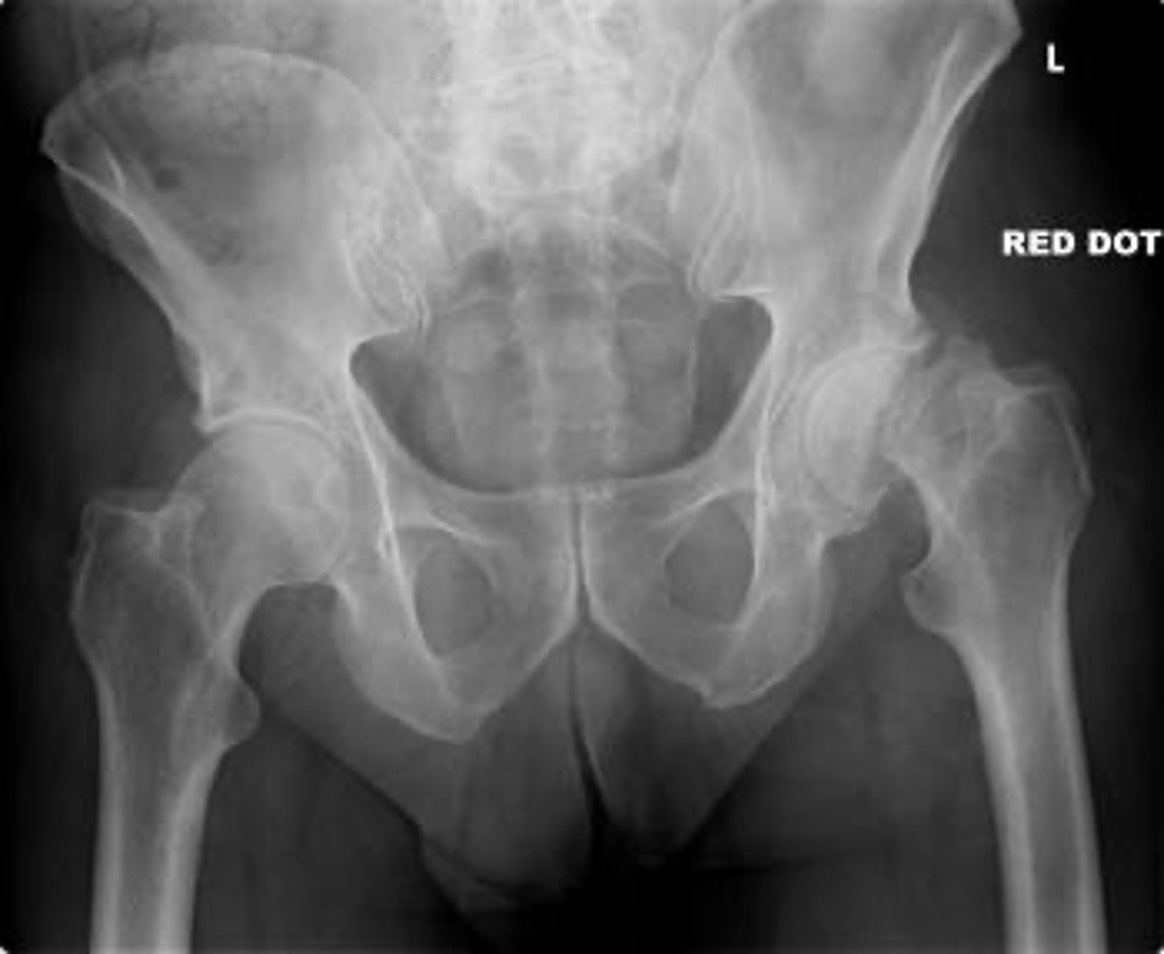

Left NOF

Intracapsular (Garden classification)

130

Intracapsular NOF fracture Garden classification type I

131

Intracapsular NOF fracture Garden classification type II

132

Intracapsular NOF fracture Garden classification type III

133

Intracapsular NOF fracture Garden classification type IV

Extracapsular (intertrochanteric) fracture

135

Extracapsular (subtrochanteric) fracture